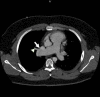

Sinus venosus atrial septal defect (SVASD) is a rare adult congenital heart disease which permits shunting of blood from the systemic to the pulmonary circulation and is commonly associated with anomalous pulmonary venous return. We report a case of a 27-year-old man with a history of premature birth and unilateral cryptorchidism who was admitted for syncope. Electrocardiogram (ECG) demonstrated atrial fibrillation (AF)and S1Q3T3 pattern along with an incomplete right bundle branch block. Transthoracic echocardiography (TTE) suggested the presence of right ventricular pressure and volume overload and severe right ventricular and right atrial enlargement. The agitated saline study was negative suggesting no inter-atrial communication. Transesophageal echocardiography (TEE) demonstrated a superior SVASD and raised the possibility of an anomalous pulmonary venous connection. Chest computed tomography identified the right superior pulmonary vein connection to the superior vena cava. The diagnosis of SVASD poses multiple challenges from the variety of symptoms to the selection of appropriate imaging and the complexity of surgical treatment.